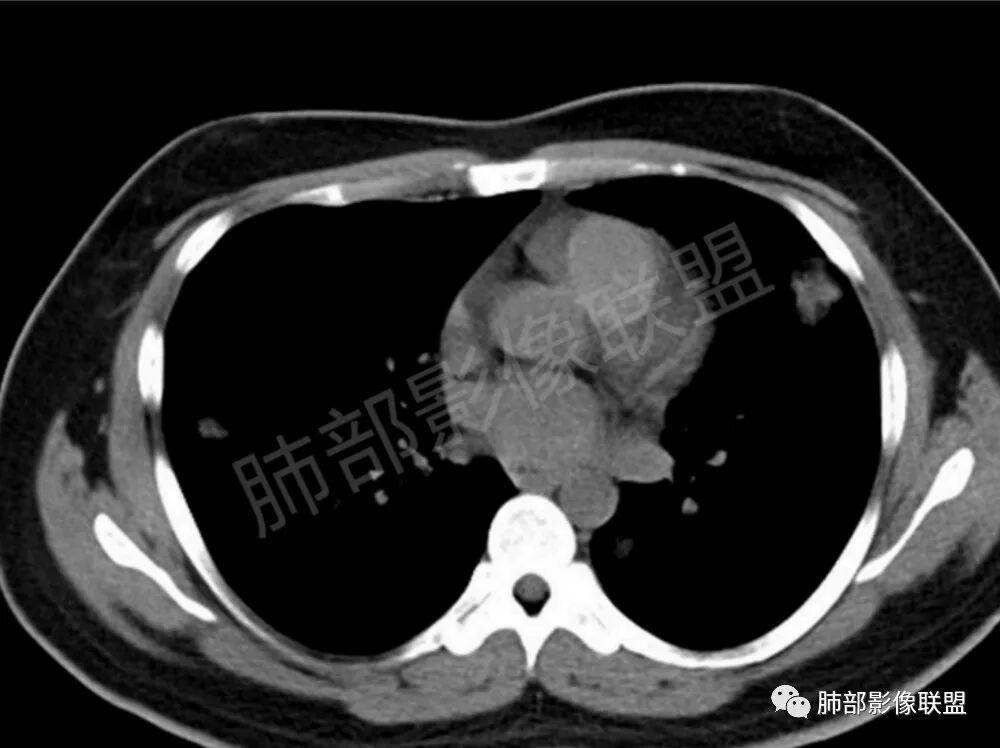

双肺多发结节影,膨隆,边缘光滑,圆顿,沿支气管血管束分布为主,部分贴胸膜,部分见空洞,空气支气管征

两肺多发结节性,大部分位于胸膜下,部分结节周围可见晕征。局部结节内可见扩张的支气管,纵隔淋巴结大,脾大,22岁男,HIV阳性,常规先考虑隐球菌。鉴别淋巴瘤,结核,马儿。

男,22,半年前咳嗽伴少痰,查HIV阳性,痰查TB阳性,既往有肺部斑片影伴空洞、纵隔淋巴结肿大、脾大。SCC、CA50、CA199、FER增高,此次胸部CT:两肺多发结节影,部分沿血管束分布,部分贴胸膜下,大小不一,密度不一,部分较散、边缘模糊,部分较实、圆钝、周围模糊晕,部分结节有支气管进入穿行自然,部分结节有血管分支自如通过。考虑HI∨相关淋巴增殖类病变,淋巴瘤?LYG?鉴别PC、TB。

青年男性,半年前咳嗽,HIV阳性,结核DNA阳性,肿标糖类抗原和铁蛋白增高。外院影像有纵隔淋巴结增大伴脾大,肺部病灶空洞。现在影像:肺内多发沿支气管分布(有支气管充气征,长轴沿支气管分布)及胸膜下分布(平行于胸膜)的大小不等结节,个别伴有空洞,双侧腋窝淋巴结肿大。纵隔图片不够,是否还有淋巴结肿大未知,脾脏未显示。

1、HIV相关淋巴瘤,有HIV阳性,有纵隔及腋窝淋巴结肿大,肺内病灶沿支气管分布(中轴淋巴间质)及胸膜下分布(周围淋巴间质),有脾大,这个是必须要考虑的。但是原来的影像是肺斑片影伴空洞,又有疑问,需要穿刺明确。

影像学缺乏特征性,以支气管血管周围、胸膜下及双肺下叶周边多发结节影最多见,结节易坏死形成空洞,伴有游走性和多变性的特征,结节周围可有磨玻璃样晕征,有时也可见单发结节影、薄壁的囊状阴影或弥漫性浸润影。肺门、纵隔淋巴结肿大少见, 可见胸腔积液和气胸。

肿块型∶表现为两肺多发大小不等的不规则肿块,肿块边缘不光整、欠锐利,有大的分叶,毛刺少见,增强扫描呈明显强化,可合并坏死、空洞;